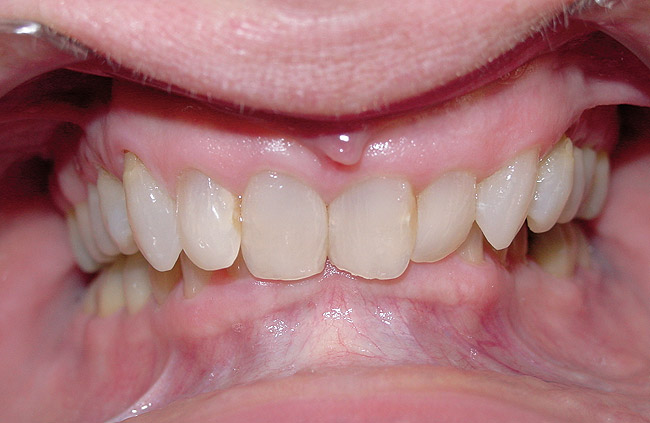

Figure 6  The inclination of the canines provide  the midline position of the mandible. When these  teeth are inclined (eg, the right canine in this  case), they tend to shift the mandible away from  the midline (in this case toward the left).

Figure 6

Figure 7  The left side of the patient shows how  maxillary molars and premolars can cause the  mandibular molars to be lingually inclined as  the teeth come into occlusion.

Figure 7

Figure 8  This case shows the shift of the  mandible from the point of first contact to full  closure because of the anterior restriction, which  has caused the mandible to shift posteriorly and  to the left. This patient experienced symptoms  of right lateral pterygoid tenderness with left  TMJ pain, left-sided headaches, and neck stiffness.  Release of this restriction allowed the  mandible to reposition itself to the midline with  reduction of the symptoms.

Figure 8

The position, shape, length, and inclination of the maxillary canines will affect the anterior frenal midline position of the mandible. This position may or may not coincide with the midline of the teeth, but gives an indication of the location of the left and right condyles in their fossae. The canines serve as lateral positioners of the mandible. The more lingual the maxillary canine inclination on one side, the more the mandible will shift to the opposite side and the condyle distalize on the opposite side (Figure 6, Figure 7 and Figure 8).

Fu and colleagues demonstrated that when the lateral occlusal fence is eliminated, the mandible will shift toward the midline.15 Patients with this type of fence usually present with tenderness in the lateral pterygoid. Shifting the mandible toward the midline tends to alleviate tenderness to palpation of this muscle. In addition, as the mandible moves to the midline, the condyle of the side the mandible will travel forward and medially so as to create the perception of an open bite.